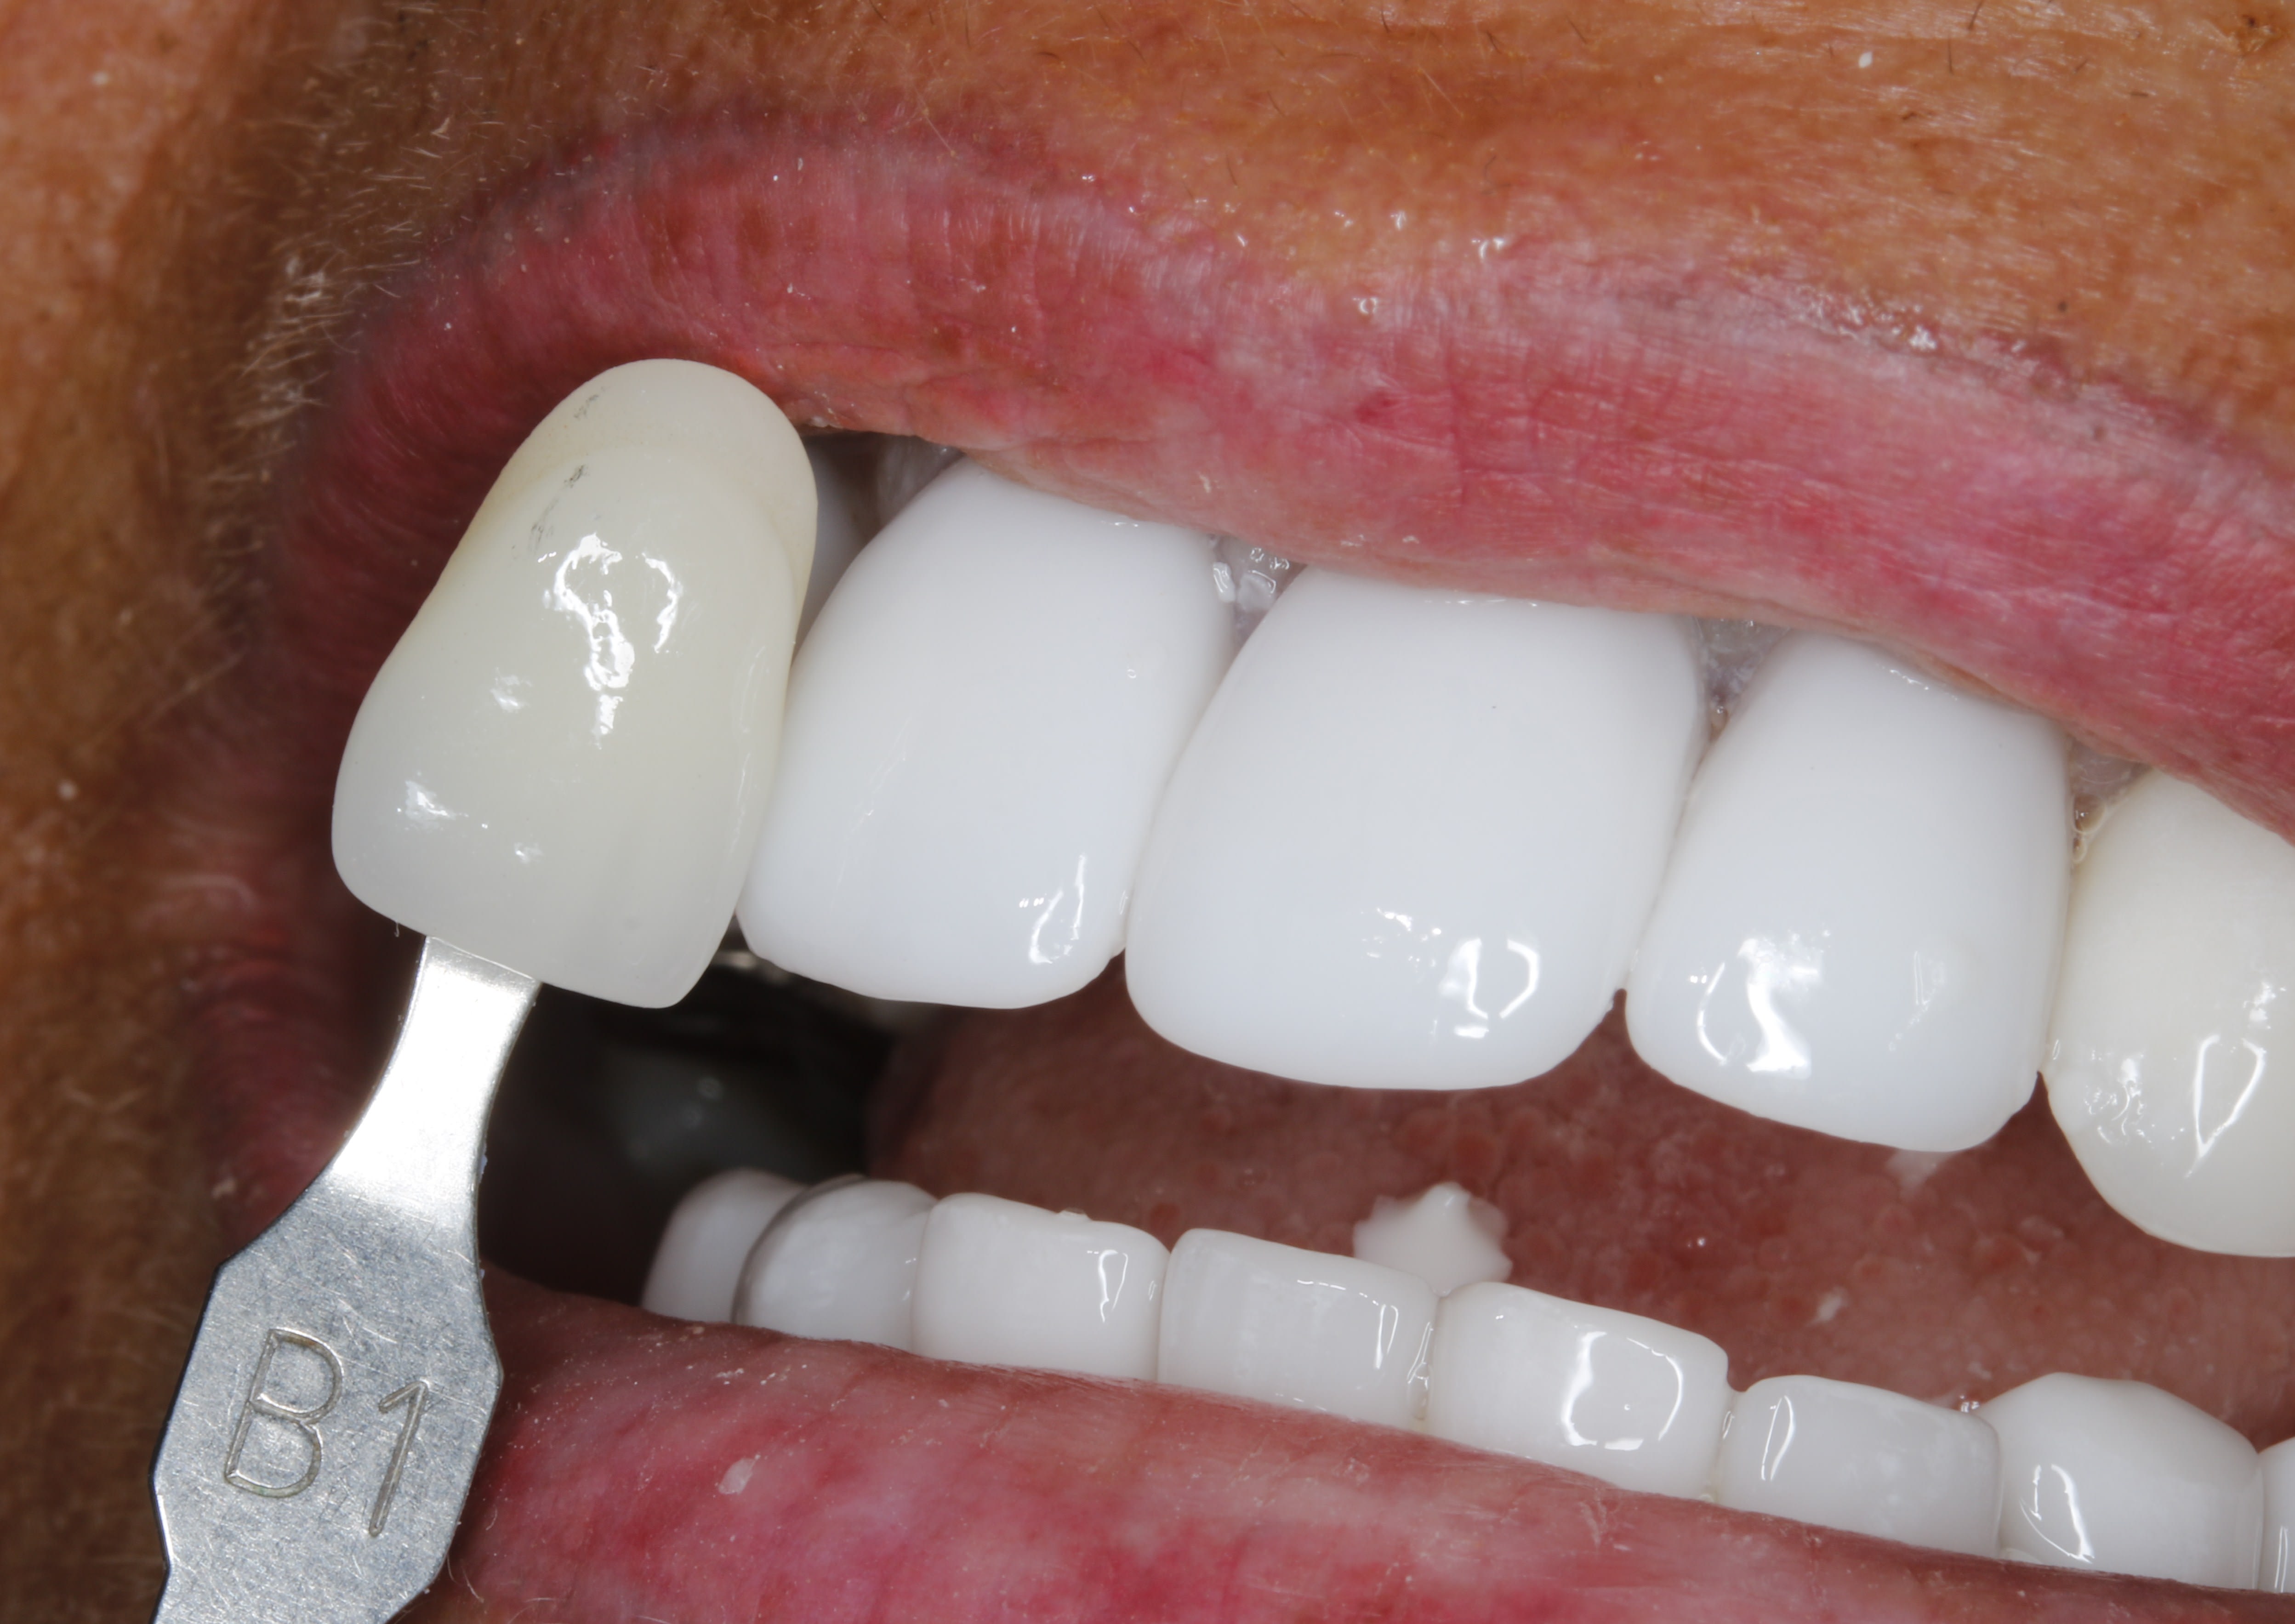

voilà , refait à l'américaine , elle est contente .

bleach

fond de teint

U.V

le combo Julio Iglesias